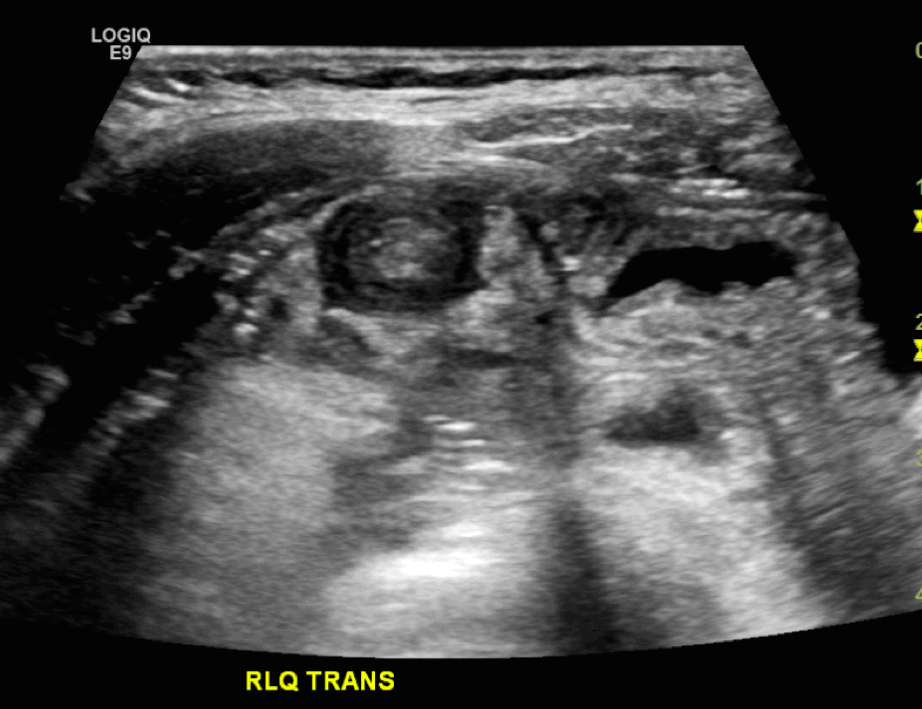

Ultrasonography is the preferred diagnostic study for many clinicians. Its sensitivity and specificity approach 100% when performed by an experienced ultrasonographer. The classic ultrasound findings include a “bull’s eye,” “coiled spring,” or “target sign.” Additionally, ultrasound can identify a lead point in many cases of intussusception associated with underlying pathology. Color duplex imaging can also demonstrate a lack of perfusion and signs of ischemia.

Figure: Target sign on ultrasound. Image courtesy of Behrang Amini. Used under the Creative Commons Attribution-Noncommercial-Share Alike 3.0 Unported license.

Figure: Target sign and pseudo-kidney. Image courtesy of Tee Yu Jin. Used under the Creative Commons Attribution-Noncommercial-Share Alike 3.0 Unported license.